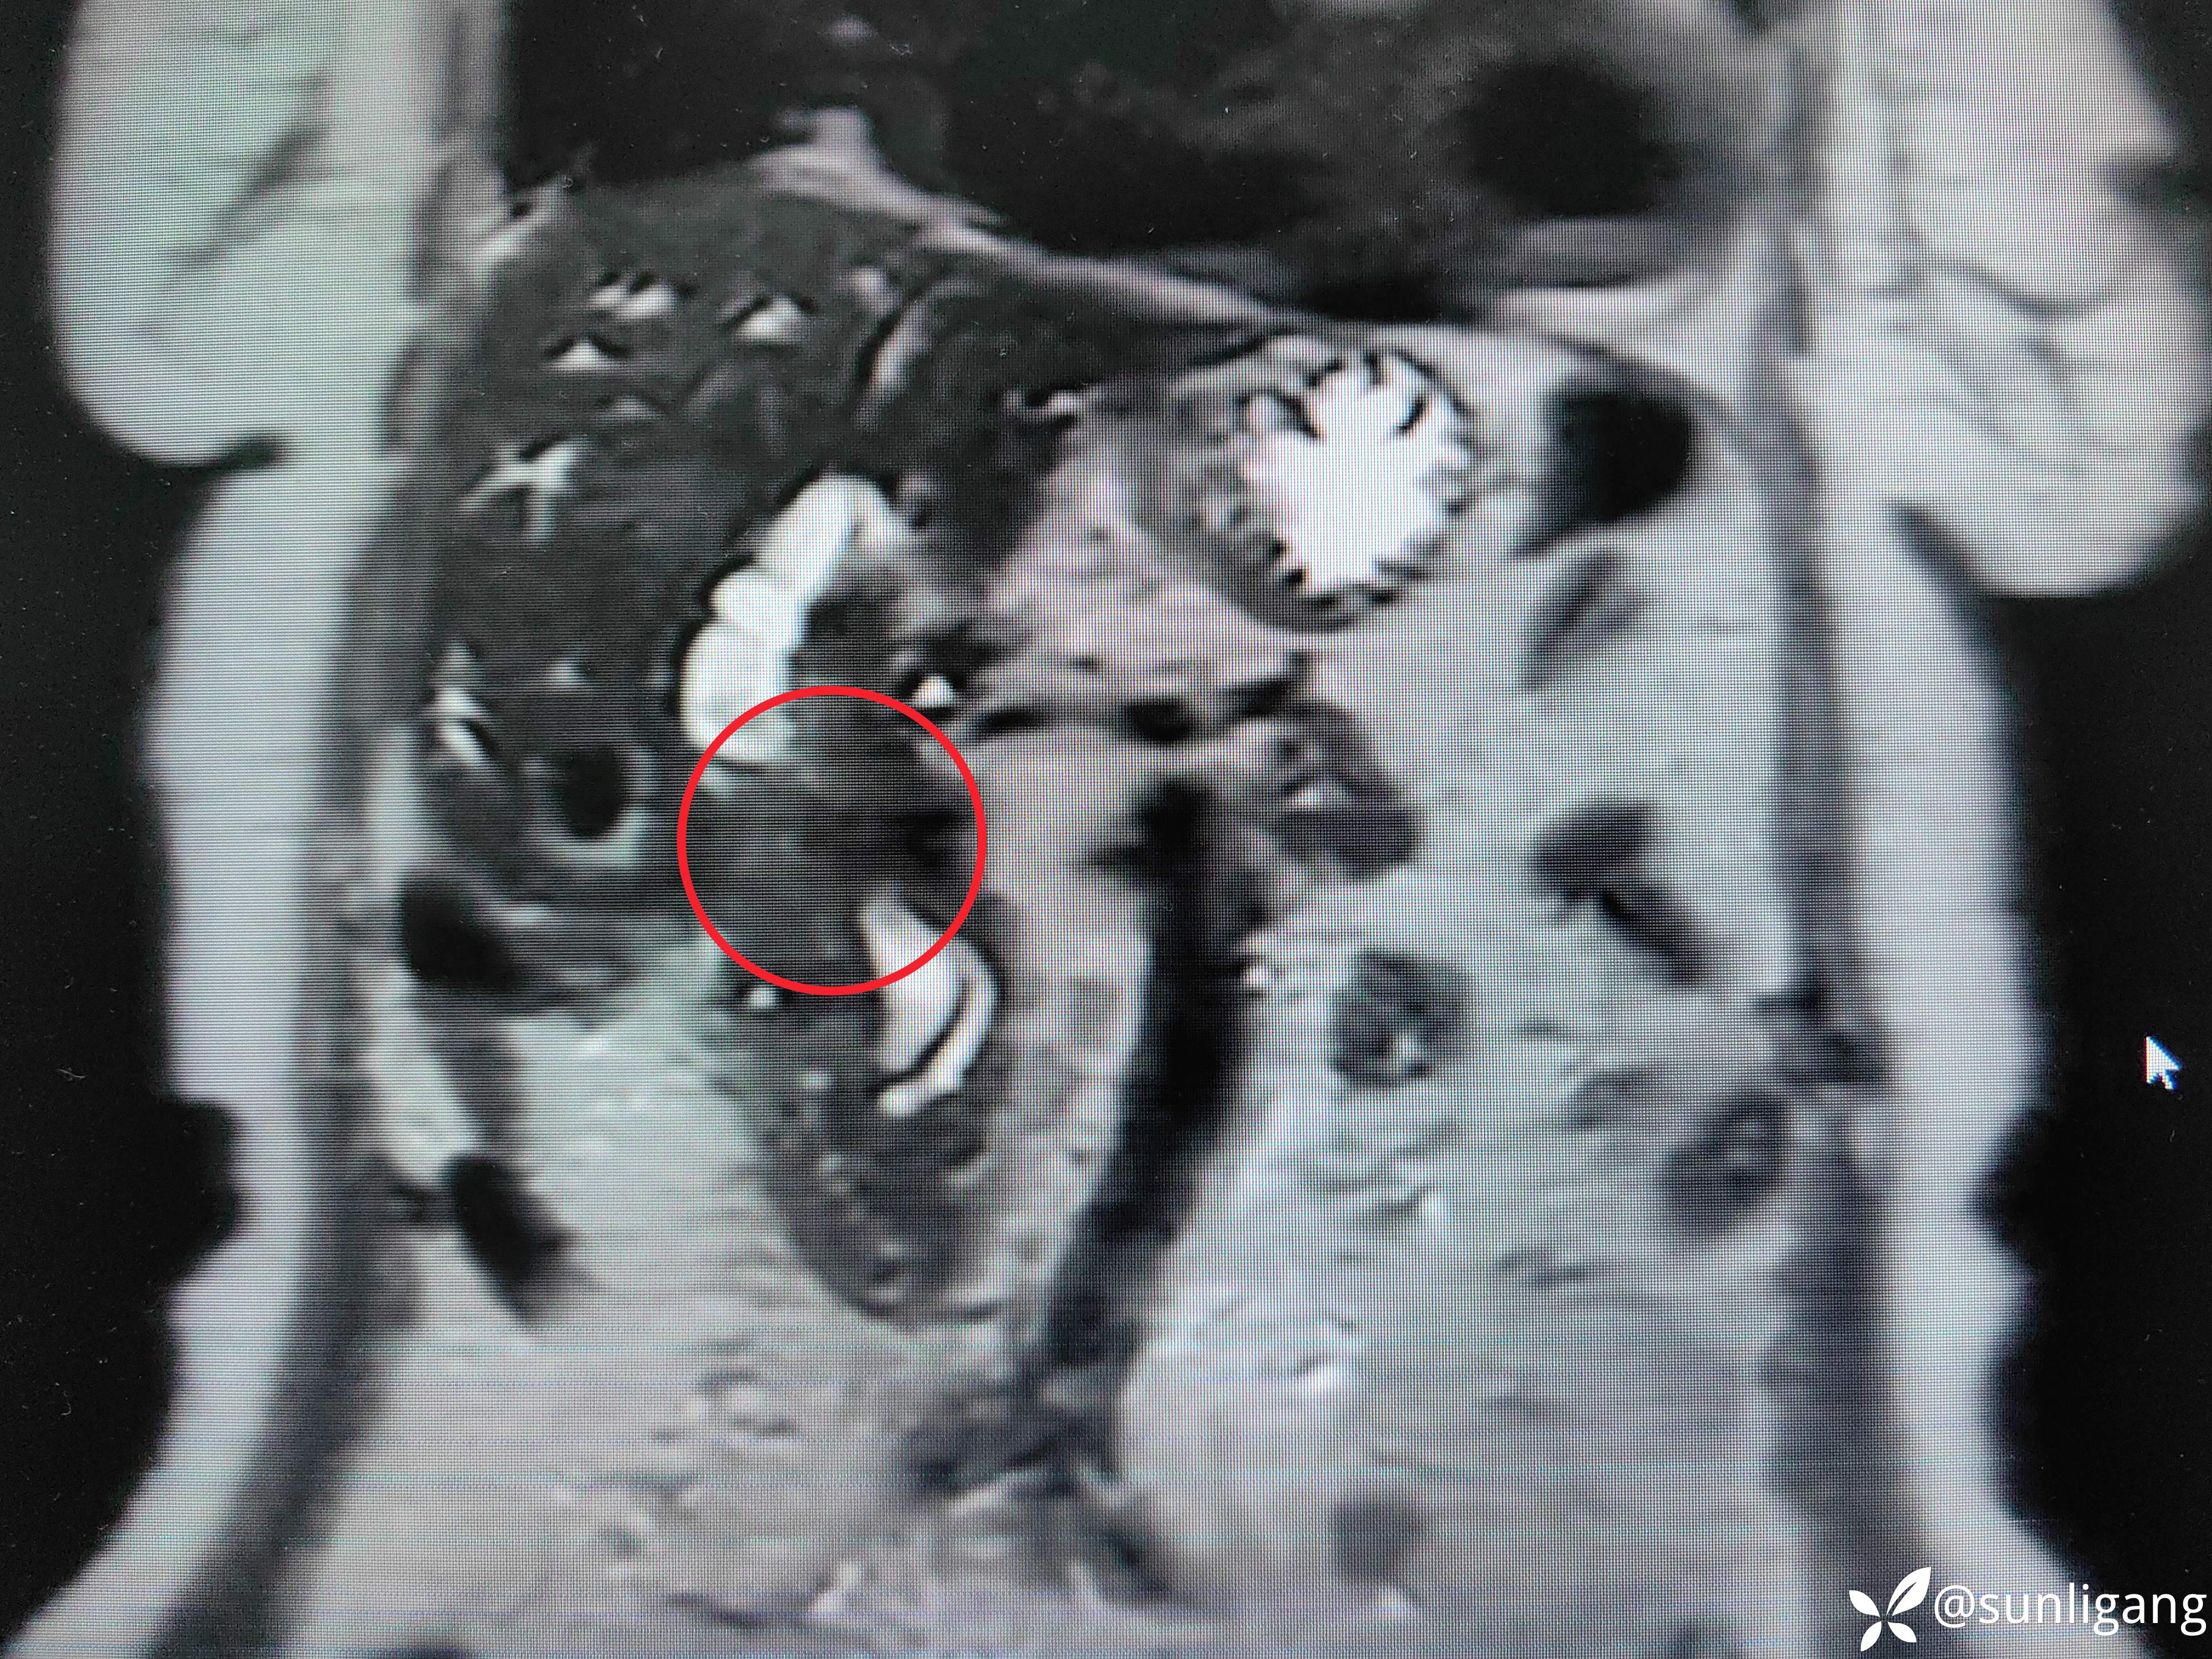

磁共振:

可见明显胆囊结石影

可见中断的中段胆管影以及扩张的肝总管、正常的胰管

可见明显变窄的胆总管(肿瘤直接侵犯?压迫?)